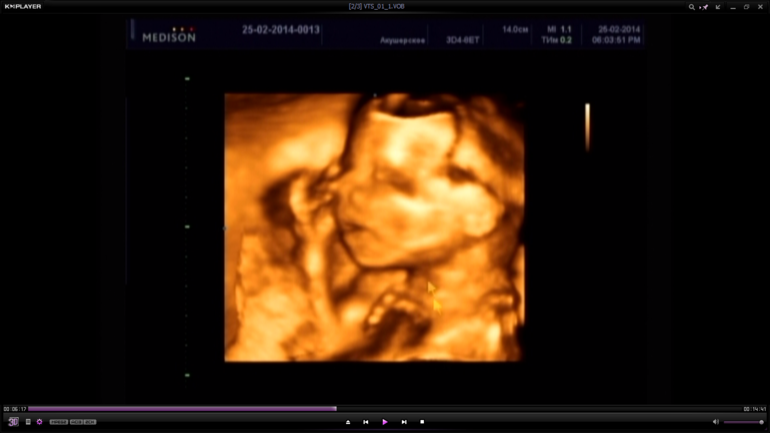

Ну и последний скрининг в 32 недели, наш вес 2058 гр. Мы уже заметно подросли что не помещались на экран))) Доча упорно закрывалась ручками и не захотела показывать свое лицо, в итоге ни одной нормальной фотки так и не получилось(((